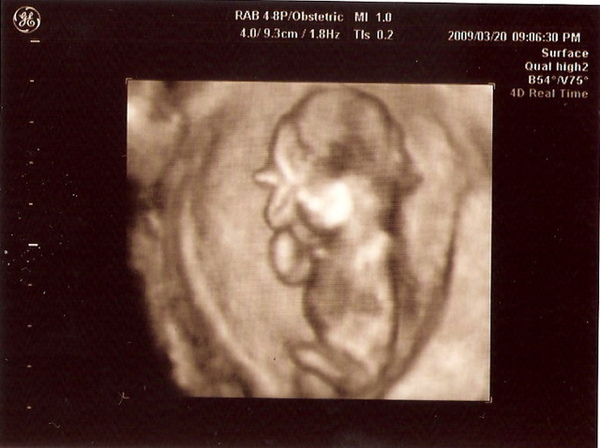

哈~~~我知道這照片有點驚悚~

不過也代表小牛弟的眼睛、鼻子已經長出來囉~

下個月嘴唇就會長出來,到時候就是要看有沒有兔唇了~(緊張)

醫生也說,下個月肉長出來後,照出來會"比較"好看,是"比較好看"哦!

這張就是單純的側身照~

在側身的"身"用上頭,有一點點黑影子,那裡就是心臟~

其它的器官還沒長~

目前身長約10公分,頭圍約4公分~